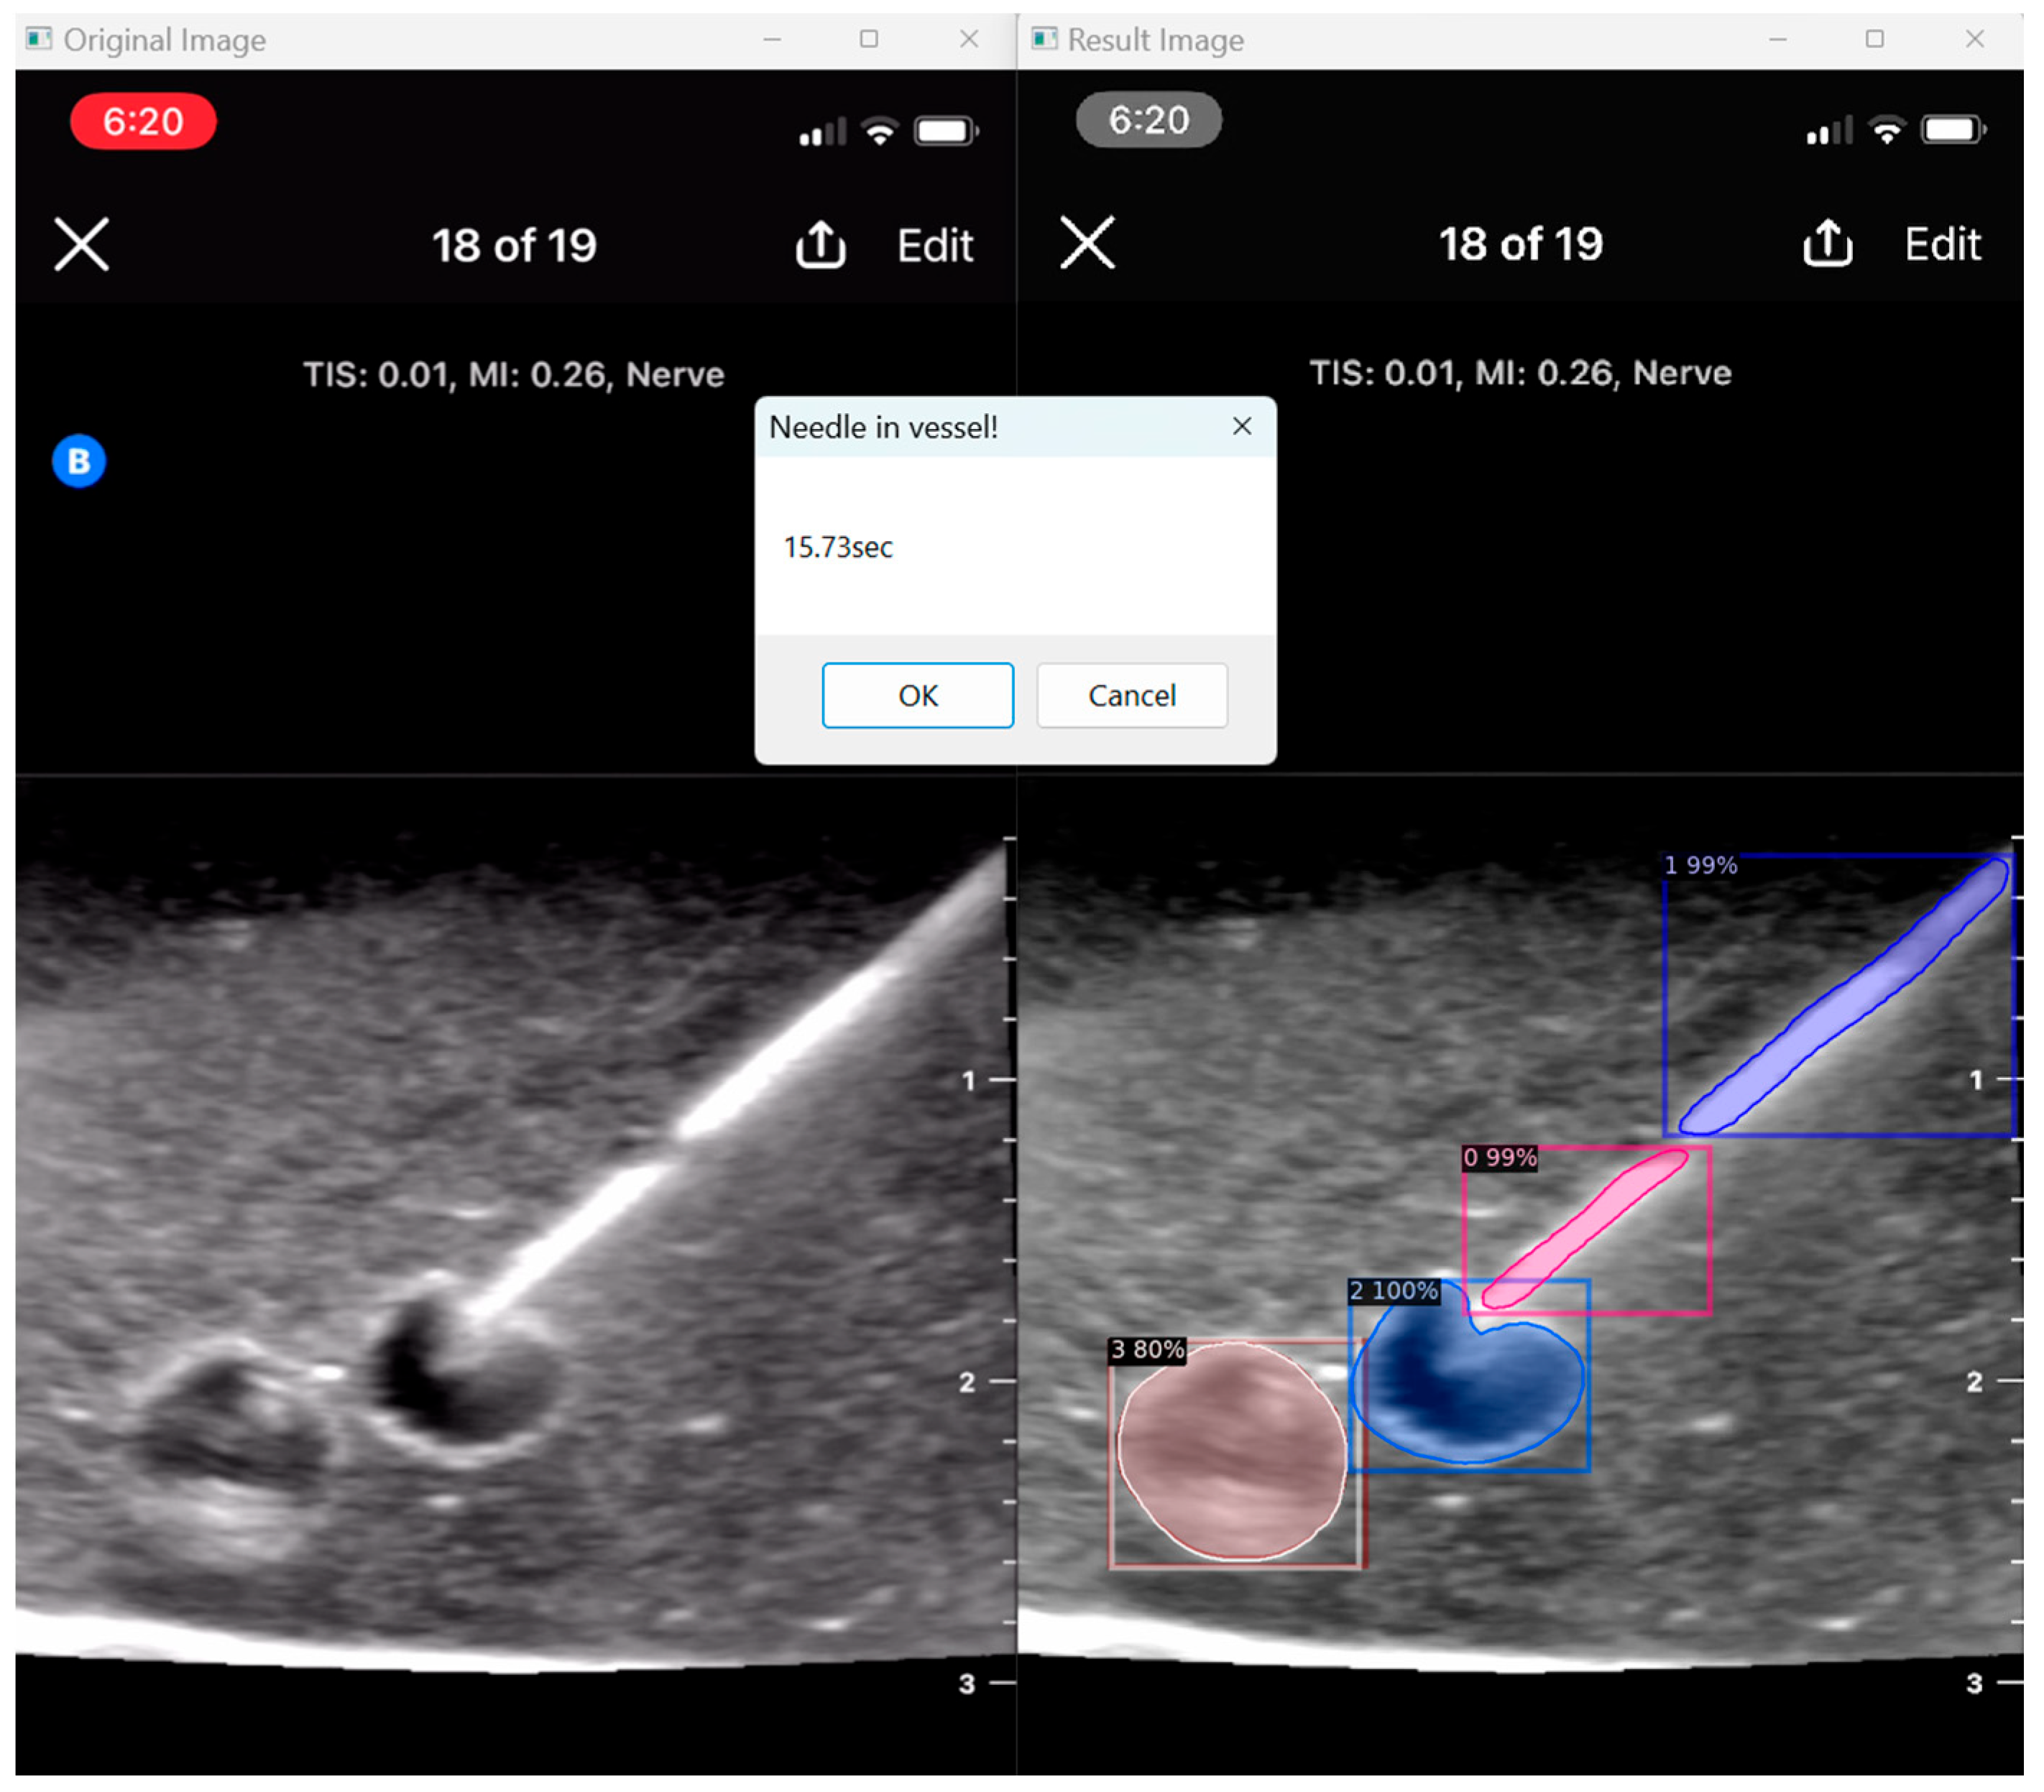

3.5. User Assessment

Our program presents an opportunity to automate ultrasound skill assessment over time, testing parameters like user speed (time taken for target structure penetration; Figure 9) and accuracy. With the automated segmentation of needle tip (item class 0) apart from needle body (item class 1), our program has the capacity to assess the percentage of frames for which a user keeps the full needle (including the tip) in view during their procedure. The capacities of AI in further assessment are vast, and possible features that can be expounded on include testing probe positioning and needle angulation.

Figure 9. User speed assessment.